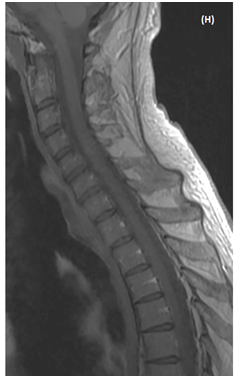

MRI follow-up at 10 days showed animprovedintramedullary T2 hyperintensity and enhancement, but therewas a residualenhancing nodule at the C4-C5 level (Figures 1F & 1G). At 6months follow-up the neurological examination was unchanged and MRI showed a faint enhancement of the spinal cord at the same level (Figure 1E).

Figure 1 MRI of an intramedullary cervical spinal cord abscess.

(A) T2-weighted sagittal view of the cervical spine shows intramedullary hyper signal intensity from medulla to T4 level together with expansion of the spinal cord, consistent with edema. Note the central area of necrosis at C4-C5 level. T1-weighted sagittal (B) and axial (C) post-contrast images, showring-enhancement of the lesion at C4-C5 level. The vertebral bodies are intact without disc space infection, epidural collection, or sub dural empyema. (D)The enhancing part of the lesionis slighly hyper intense on sagittal Diffusion-weighted (DW)« focus » sequence (E) Restricted diffusion is visible as a dark dot inside the necrotic area on ADC map (arrow). Follow-up MRI of cervical spine (T1-weighted sagittal (F) and axial (G) post-contrast images performed 14 days after initiation of antibiotic treatment shows partial resolution of the lesion. h -At 6 month-MRI follow-up the lesion has disappeared.